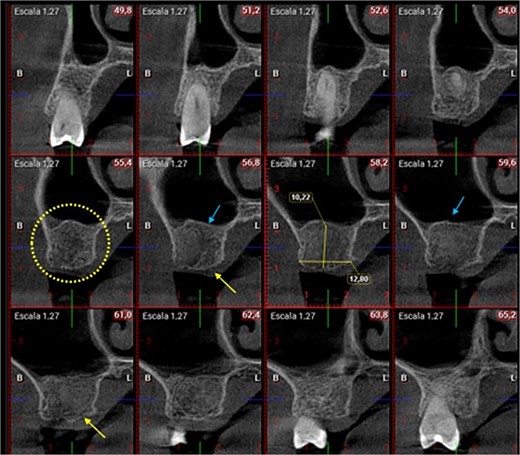

A 56-year-old female patient without any systemic diseases was referred by otolaryngology for evaluation by oral surgery due to presenting pain on the left side of the face for two weeks. The patient’s first molar presented a wide restoration (Fig. 1). This molar had undergone endodontic treatment some years ago. The CT scan showed a hyperdense left maxillary sinus almost entirely with loss of continuity of the maxillary sinus floor at the level of the left upper first molar involving the furcation zone, it is evident an oroantral communication of 7 mm (Fig. 2). The patient referred to spontaneous pain during chewing. Based on the CT scan and the clinical findings, pharmacological management was indicated with oral antihistamine 10 mg every 24 hours for 10 days, Moxifloxacin 400 mg every 24 hours, and scheduled extraction with oroantral communication closure with collagen sponge on the third day after starting the antibiotic, which will be used for a total of 10 days. The patient agreed to sign an informed consent file to make the technique to extraction and close the oroantral communication.